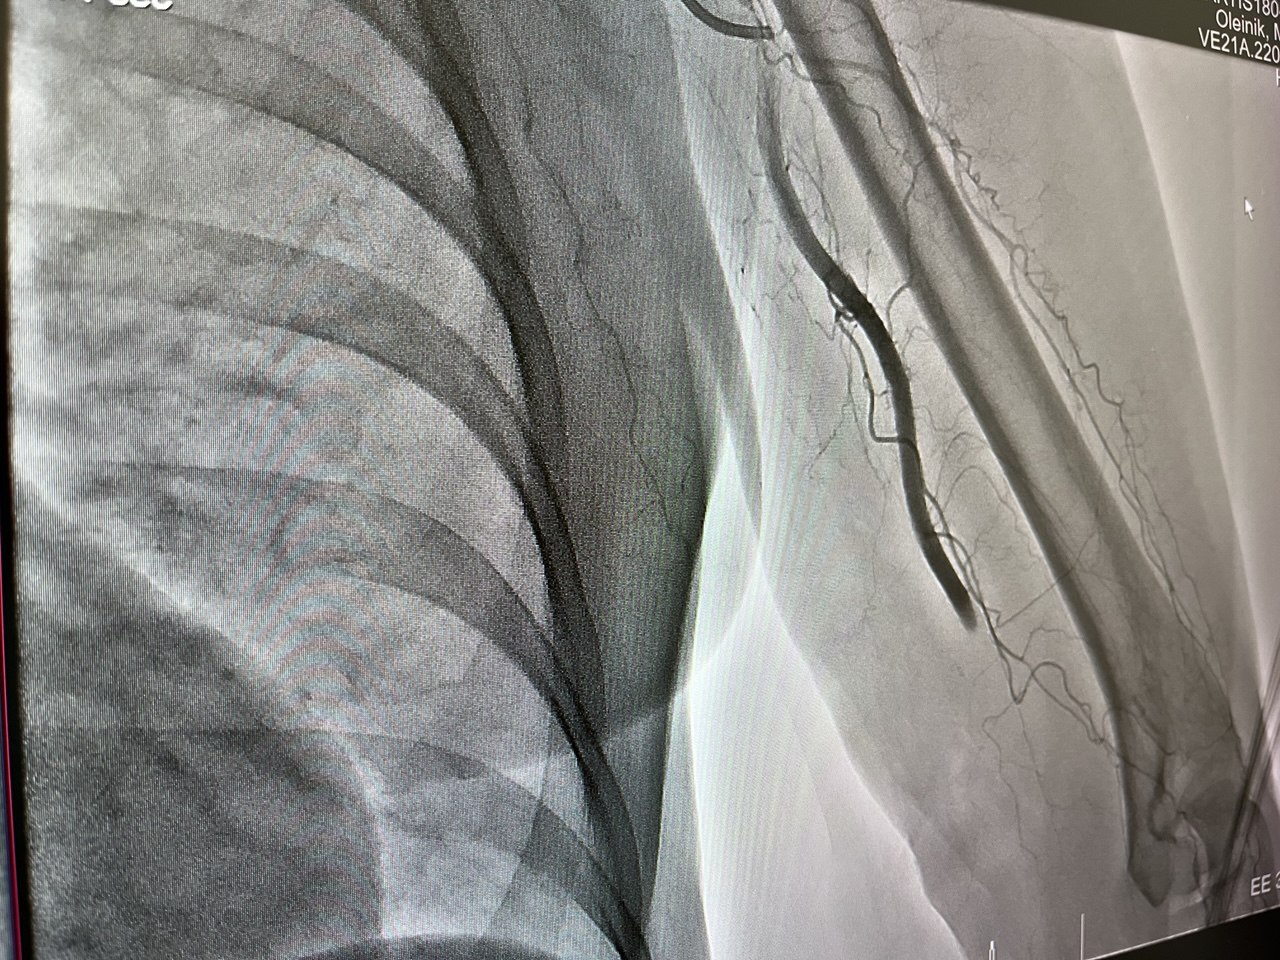

«Плохо женщине стало в транспорте – из-за резкой боли в руке потеряла сознание. По скорой ее доставили в больницу, где диагностировали тромбоз плечевой артерии левой руки», — заявил министр.

Из-за тромба женщина могла потерять руку, поэтому было принято решение оперировать. Хирурги достигли микрокатетером места закупорки сосуда через бедренную артерию и устранили тромб.

После операции очень быстро восстановилось кровоснабжение руки, теперь жизни пациентки ничего не угрожает.

Фото: Министерство здравоохранения Кузбасса